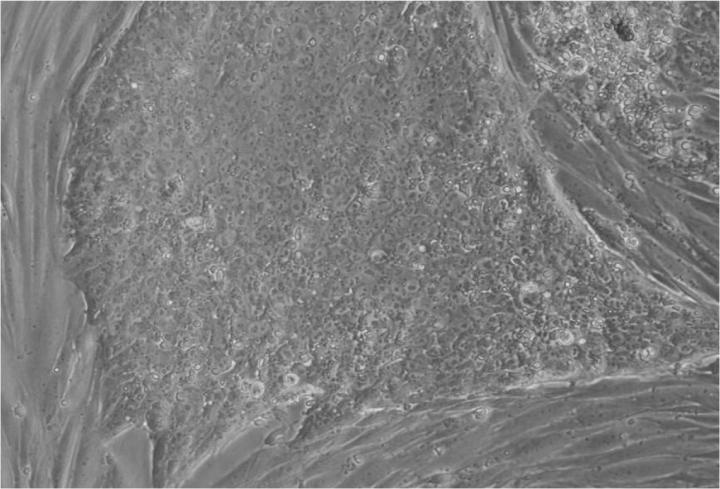

人類胚胎干細(xì)胞 (ESC) 是從囊胚(一種非常早期的人類胚胎)中發(fā)現(xiàn)的少量細(xì)胞產(chǎn)生的。從囊胚中取出的單個細(xì)胞生長成大量細(xì)胞以產(chǎn)生 ESC“系”。

胚胎干細(xì)胞的自我復(fù)制能力允許從干細(xì)胞系中培養(yǎng)出大量細(xì)胞,并與全球?qū)嶒?yàn)室共享多年,從而最大限度地減少了從囊胚制造新胚胎干細(xì)胞的需求。

Jenny Nichols 拍攝的人類囊胚和人類胚胎干細(xì)胞圖像。愛丁堡大學(xué) MRC 再生醫(yī)學(xué)中心向 SCNT 和多莉羊注射細(xì)胞核。